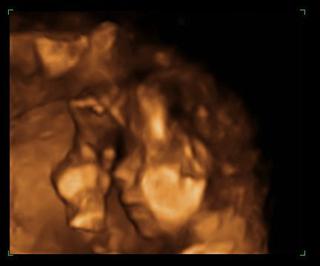

@rianka7 ano u palla robia 4d utz stal po starom okolo 2000sk. bola som u neho na morfologickom a neodporucam.. mna osobne sa dost dotkol, kedze som mala robeny utz viacerymi lekarmi a nikto nemal problem pozriet, krasne bolo vsetko vidiet a on mi povedal,ze nevidi,lebo mam vela tuku.. pre porovnanie foto od palla to oranzove a foto zo 4d z KE . bola som u dr.Dankovcika cena zhruba to iste, zazitok neskutocny mam cd s fotkami a videami z utz..